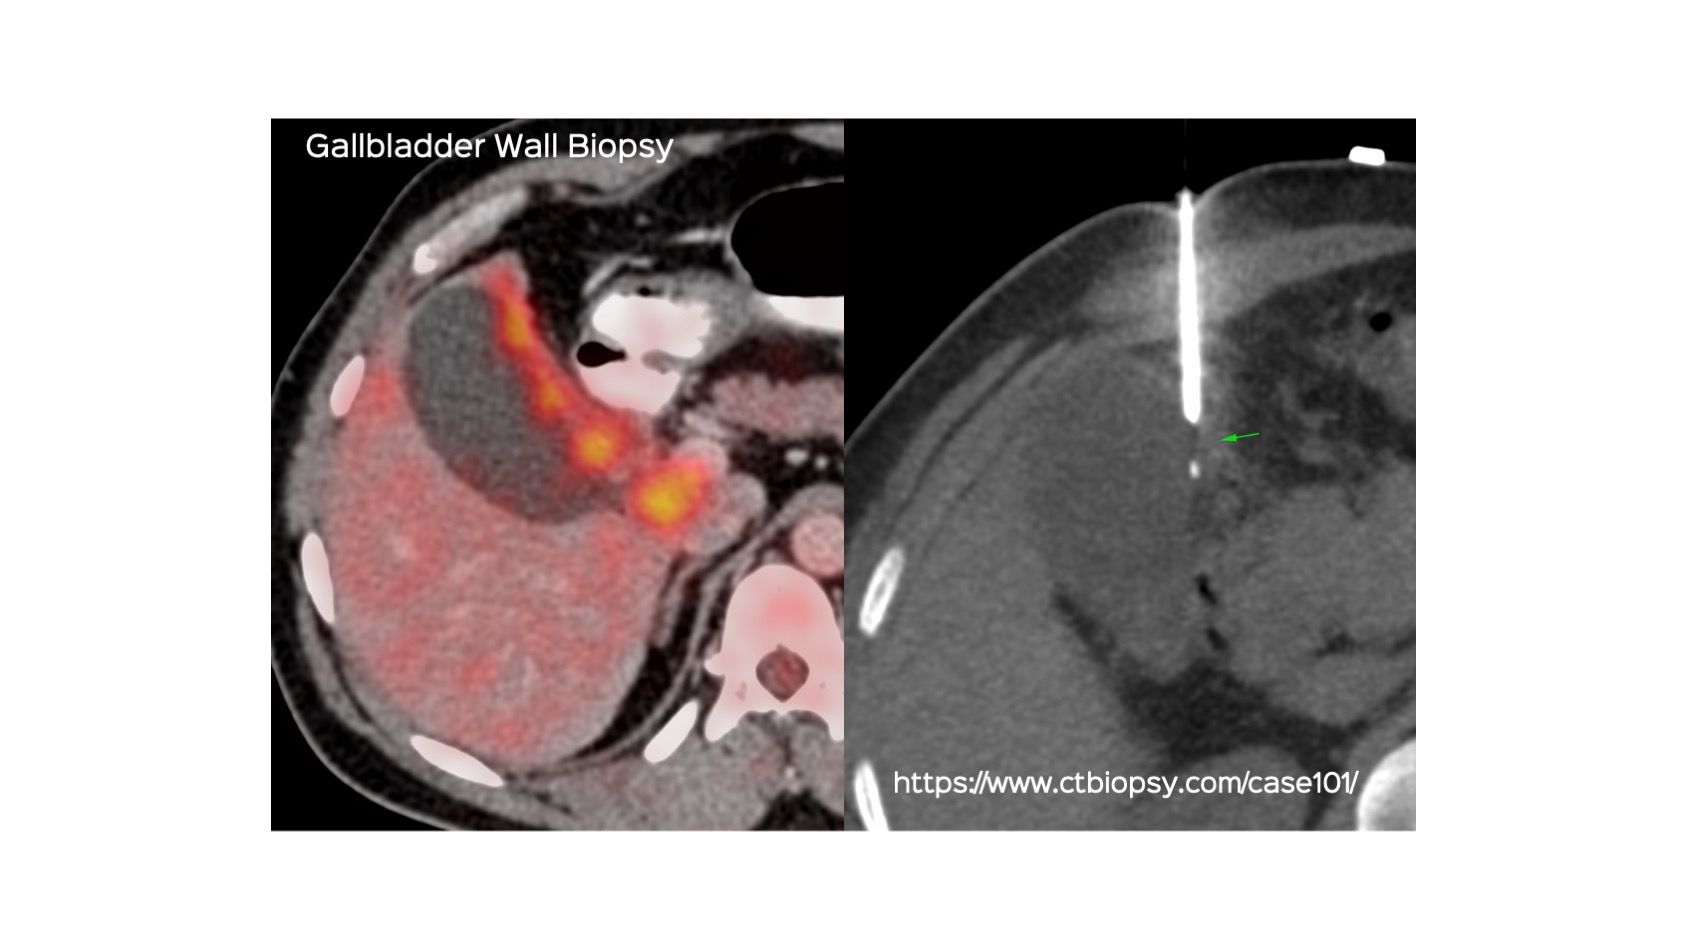

Case 101: Gallbladder Wall Biopsy